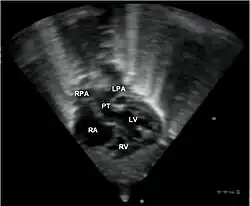

Abbreviations: RA=right atrium, RV=right ventricle, LV=left ventricle, PT=pulmonary trunk, LPA and RPA=left and right pulmonary artery.